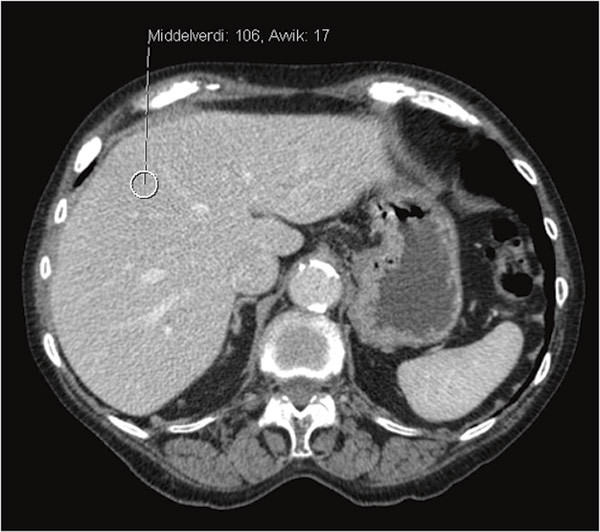

Det ble utført CT-undersøkelse av leveren, som viste patologisk forhøyet signal med gjennomsnittlig tetthet 100 HU (Hounsfield Units) (fig 2, fig 3), klart forenlig med jernavleiring i lever. På bakgrunn av dette ble sannsynligheten for toksisk oppladning i leveren vurdert som så stor at risikoen ved en leverbiopsi ikke var rettferdiggjort. Det ble også gjort MR cor ved universitetssykehuset, der T2-vektet bilde viste maksimalt patologiske verdier på < 10 ms (> 20 ms), forenlig med jernavleiring i myokard (fig 4). Vi fant ingen validert måte å måle jernavleiring i pancreas og thyreoidea på.